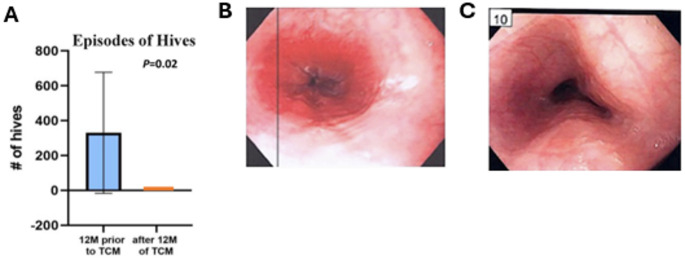

Abstract Image